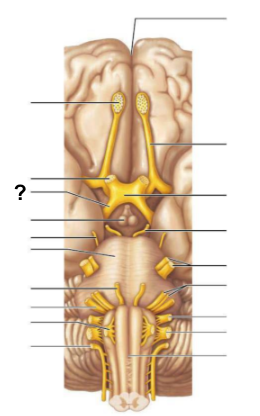

What structure, labeled “?”, is the starting point of cerebrospinal fluid circulation in the brain?

Lateral ventricle

From the lateral ventricles, CSF flows through which structure, labeled “?”, to reach the third ventricle?

Interventricular foramen

After the third ventricle, CSF flows through which narrow passage, labeled “?”, to reach the fourth ventricle?

Cerebral aqueduct

What are the two apertures, labeled “?”, through which CSF exits the fourth ventricle to enter the subarachnoid space?

The median aperture and the lateral apertures

Which structure surrounds the brain and spinal cord, allowing CSF to circulate?

Subarachnoid space

Through which structure, labeled “?”, is CSF absorbed into the venous blood?

Arachnoid villi

Into which venous system does CSF drain after passing through the arachnoid villi?

Dural venous sinuses

What is the function of the central canal in CSF circulation?